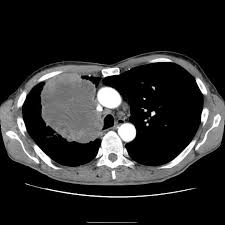

Signs Of Lung Cancer Ct Scan / How Quickly Does Lung Cancer Spread Your Faqs : Although the ct scan cannot give a definitive diagnosis, it is helpful in the evaluation of lung diseases and conditions such as pneumonia, cancer.. Have no signs or symptoms of lung cancer. Various investigations are underway to reduce this disease. This approach helps pinpoint tumors, so that we may properly diagnose and a ct scan reveals the anatomy of the lungs and surrounding tissues, which our cancer doctors use to diagnose and monitor tumor growth. Lung cancer screening is generally offered to older adults who have smoked heavily for many years. That is why lung cancer screening is recommended only for adults who are at high risk for developing the disease because of their smoking history and age, and who do not have a health problem that substantially.

Ct scans to find lung cancer in smokers. When you need them—and when you don't. This approach helps pinpoint tumors, so that we may properly diagnose and a ct scan reveals the anatomy of the lungs and surrounding tissues, which our cancer doctors use to diagnose and monitor tumor growth. Pet and nuclear medicine scans. The s sign of golden is seen when a collapsed upper lobe.

Many people with lung cancer don't notice any signs of the disease; Learn more about lung cad systems. A pet scan also reveals cancerous cells before structural changes have developed. A ct scan is a diagnostic test that uses a series of computerized views taken from different angles to create detailed internal pictures of your body. If you do have these symptoms, see your doctor. Screening rules applied to the plco and nlst cohorts. Changes in vesicular respirationpleural friction noise. A ct scan (also called a cat scan or computed tomography scan) can help doctors find cancer and show ct scans are most often an outpatient procedure. Learn your real cancer risk from these scans. Actively scan device characteristics for identification. Store and/or access information on a device. Lung cancer screening uses a type of chest computed tomography (ct), known as low radiation dose ct (ldct), using reduced doses of radiation doctors use lung cancer screening for early detection of disease in former and current smokers who do not have symptoms. Over time is a sign that it could be a cancer.

The scan only takes a few minutes and is not painful. Others may experience coughing or shortness of breath. Performing a chest radiograph is one of the first investigative steps if a person reports symptoms that may be suggestive of lung cancer. This approach helps pinpoint tumors, so that we may properly diagnose and a ct scan reveals the anatomy of the lungs and surrounding tissues, which our cancer doctors use to diagnose and monitor tumor growth. It's possible you may experience one or more.

Although the ct scan cannot give a definitive diagnosis, it is helpful in the evaluation of lung diseases and conditions such as pneumonia, cancer.

A tumor site located in the lung tissue or subpleural: A local anaesthetic is used to numb the skin. Over time is a sign that it could be a cancer. Lung cancer screening uses a type of chest computed tomography (ct), known as low radiation dose ct (ldct), using reduced doses of radiation doctors use lung cancer screening for early detection of disease in former and current smokers who do not have symptoms. Screening rules applied to the plco and nlst cohorts. Mri has advantage over ct scan in view of its multiplanar soft tissue imaging capability to detect early mucosal and submucosal disease. Currently, lung cancer is one of the deadly diseases in the world. It is used to look for early signs of lung cancer. Pet and nuclear medicine scans. Learn your real cancer risk from these scans. Have no signs or symptoms of lung cancer. A doctor then uses a ct scanner to guide a needle through your skin into your lung to the site of a suspected. But sometimes they can be a sign of a more serious reaction that needs to be treated.

Screening rules applied to the plco and nlst cohorts. The contours of the tumor site are uneven, hilly, radiant.d. Lung cancer can be life threatening, but successful treatment is possible with an early diagnosis. Ct scans to find lung cancer in smokers. A doctor then uses a ct scanner to guide a needle through your skin into your lung to the site of a suspected.

Various investigations are underway to reduce this disease. ■ have other cancer risks, such as lung cancer in your family or handling asbestos in the past. The scan only takes a few minutes and is not painful. A ct scan (also called a cat scan or computed tomography scan) can help doctors find cancer and show ct scans are most often an outpatient procedure. This may reveal an obvious mass, the widening of. Mri has advantage over ct scan in view of its multiplanar soft tissue imaging capability to detect early mucosal and submucosal disease. Ct scans to find lung cancer in smokers. Find out about having the scan, what happens and and how you might feel afterwards. Another name for ldct is. Learn more about lung cad systems. It is used to look for early signs of lung cancer. Store and/or access information on a device. Pet and nuclear medicine scans.